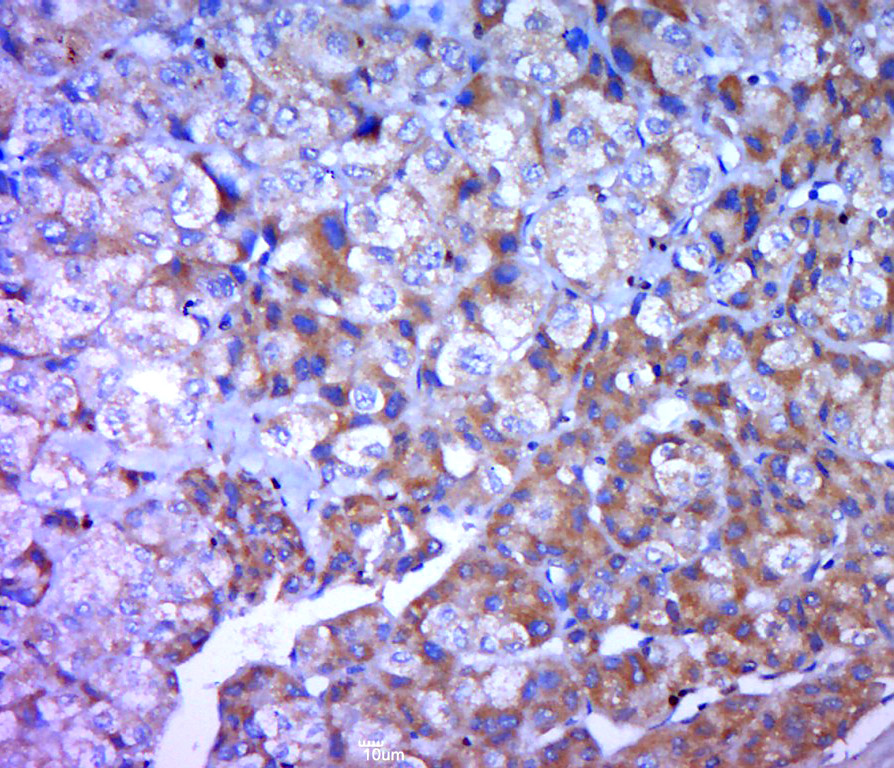

Paraformaldehyde-fixed, paraffin embedded (human liver carcinoma); Antigen retrieval by boiling in sodium citrate buffer (pH6.0) for 15min; Block endogenous peroxidase by 3% hydrogen peroxide for 20 minutes; Blocking buffer (normal goat serum) at 37°C for 30min; Antibody incubation with (Fibrinopeptide A) Polyclonal Antibody, Unconjugated (bs-10080R) at 1:400 overnight at 4°C, followed by a conjugated secondary (sp-0023) for 20 minutes and DAB staining.